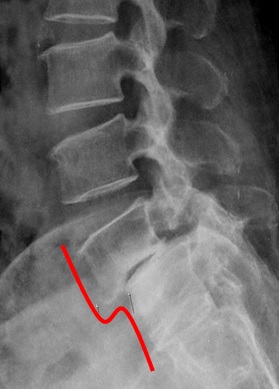

* 척추전방전위증.

척추전방전위증은 척추의 뼈가 하나씩 미세하게 이동하여 척추의 전방으로 이동하는 질병입니다.

이러한 이동은 일반적으로 척추의 안정성을 약화시킵니다.

척추전방전위증의 증상에는 목과 등의 통증, 척추의 굴곡각도 증가, 신경증상 등이 있습니다. 이러한 증상은 중등도에서 심각한 수준까지 다양할 수 있습니다.